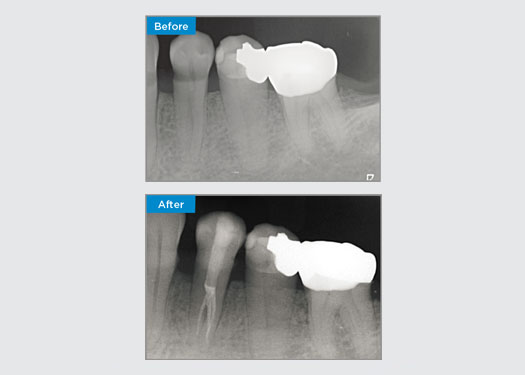

Der Patient stellte sich mit einer irreversiblen Pulpitis an Zahn 46 vor. Auf dem präoperativen Röntgenbild zeigt sich Zahn 46 mit einer zusätzlichen distalen Wurzel (Radix Entromolaris-Zahnmorphologie). Ein DVT-Scan hat das Vorhandensein einer DL-Wurzel mit starker Wurzelkrümmung bestätigt. Für diese kritische DB-Wurzel ist eine sorgfältige Feilenauswahl entscheidend.

In dieser Situation ist die Erhaltung der Zahn-/Wurzelstruktur von entscheidender Bedeutung, um das Risiko von Vorsprüngen, Verschiebungen, Abrissen, Perforationen und Wurzelfrakturen zu verringern. Fallauswahl, Diagnose und Behandlungsplanung sind wichtig. Die Auswahl von endodontischen Feilen, die flexibel und effizient sind und die natürliche Wurzelanatomie respektieren, ist entscheidend.